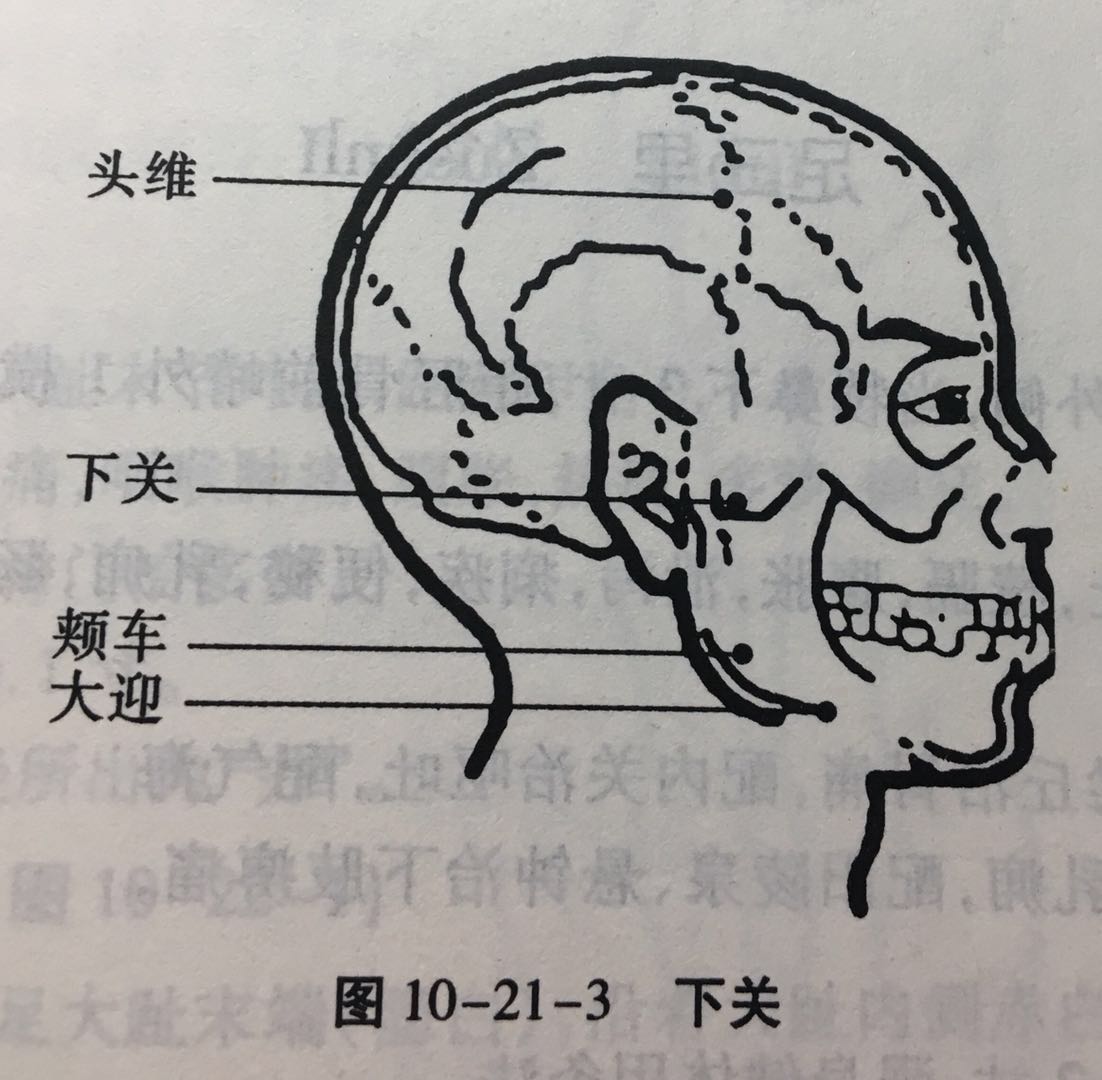

下关

【定位】 在面部耳前方,当颧弓与下颌切迹所形成的凹陷中(图 10-21-3)。

【主治】 耳聋,耳鸣,聤(tíng)耳,齿痛,口噤,口眼歪斜。

【配伍】 配翳风治耳疾。

【刺灸法】 直刺 0.5 ~ 1 寸。

【附注】 足阳明、足少阳经交会穴。